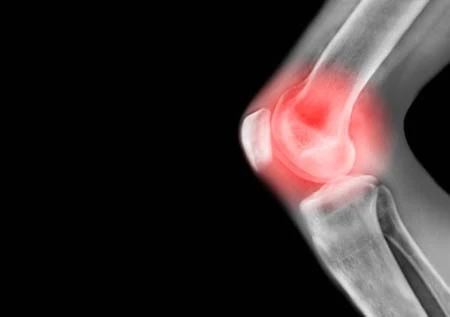

1 - Viêm xương khớp

Người nữ có nguy cơ mắc bệnh viêm xương khớp (osteoarthritis) cao gấp 3 lần so với nam giới, theo Health Family Medicine. Cách cơ thể người nữ được cấu trúc có xu hướng có nhiều các khớp linh hoạt và dây chằng đàn hồi. Sự đàn hồi này hữu ích trong thời gian người nữ mang thai và sinh con dẫn đến các bất ổn viêm xương khớp. Chính điều này làm cho người nữ có nguy cơ bị bong gân và tổn thương cao hơn.

Người nữ có nguy cơ mắc bệnh viêm xương khớp (osteoarthritis) cao gấp 3 lần so với nam giới

Ngoài ra, người nữ có phần hông rộng hơn, có thể tác động đến sự điều chỉnh của đầu gối và gây ra áp lực lên các gối. Và người nữ từ sau 50 tuổi có nguy cơ bị viêm xương khớp cao hơn.

Việc mất đi estrogen cũng có thể là một tác nhân đóng góp đến bất ổn này vì estrogen bảo vệ sụn và khớp khỏi bị viêm nhiễm.

Để giảm nguy cơ viêm xương khớp, người nữ nên thường xuyên vận động thể chất và duy trì cân nặng cơ thể khỏe mạnh - khuyến nghị của Tổ chức Viêm khớp Hoa Kỳ.